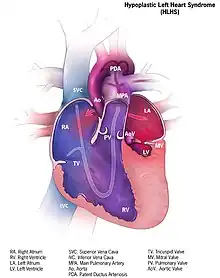

| Illustration of heart with hypoplastic left heart syndrome | |

Hypoplastic left heart syndrome (HLHS) is a rare congenital heart defect in which the left side of the heart is severely underdeveloped and incapable of supporting the systemic circulation.[2] It is estimated to account for 2-3% of all congenital heart disease.[3] Early signs and symptoms include poor feeding, cyanosis, and diminished pulse in the extremities.[4] The etiology is believed to be multifactorial resulting from a combination of genetic mutations and defects resulting in altered blood flow in the heart.[5][6][7] Several structures can be affected including the left ventricle, aorta, aortic valve, or mitral valve all resulting in decreased systemic blood flow.[8]

In typical anatomy, the left side of the heart receives oxygen-rich blood from the lungs and pumps it to the rest of the body. Patients with HLHS can have a number of cardiac malformations that ultimately lead to a diminutive left ventricle that is unable to supply sufficient blood flow to the rest of the body.[20] There are three main anatomic variants of the disease differentiated by either stenosis or atresia of the aortic and mitral valve.[20]

Mitral atresia and aortic atresia (MA-AA) subtype is the most severe form of HLHS resulting in no blood flow entering the left ventricle at all resulting in no possibility of left ventricular output.[20] In the mitral stenosis and aortic atresia (MS-AA) subtype blood is able to fill the left ventricle, however it is unable to be supplied to the systemic circulation via the hypoplastic ascending aorta.[20] Lastly, the mildest form is the mitral stenosis and aortic stenosis (MS-AS) subtype.[20] In these patients although the left ventricle is able to supply some blood flow to the rest of the body the overall left ventricular systemic output remains inadequate.[20]

In all of these cases blood is unable to be pumped to the rest of the body by the left ventricle. The neonate is reliant on blood flowing through an atrial septal defect to mix oxygenated and deoxygenated blood, and on a patent ductus arteriosus to allow blood to reach the aorta and the systemic circulation via the right ventricle. This is what defines HLHS as a "single ventricle" defect.[15]